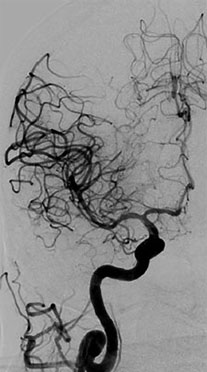

Egas Moniz dreamt of making either the brain or the cerebral vessels opaque on imaging. His efforts led to the discovery of angiography of cerebral vessels.20 In the early 20th century, he performed multiple experiments on animals and cadavers. Once confident of his method, he performed a “cutdown” to reach the carotid artery and injected contrast material directly into it making angiography possible. Loman and Myerson further refined the technique by allowing percutaneous access to the carotid artery and injecting contrast material without “‘cutdown” procedure.21 Angiography of the vertebral arteries was discovered approaching it through the brachial, subclavian, and vertebral arteries over the next few years.22 The most famous Seldinger technique, using a catheter instead of a needle, was devised in 1953, but it took almost 10 years to be used in cerebral angiography.23,243

The transfemoral approach was also developed along the same time and was accepted quite late. The technique kept improving with the help of technological advances such as digital subtraction, safer contrast agents, magnification technology, and multiple planes of imaging. Glue, particles, coils, and Onyx were discovered for intravascular procedures (Figure 1.3).

The procedure has withstood the early complications25 and the modern day cerebral angiography does not require any general anesthesia and takes much shorter time, thus reducing the incidence of the known complications.

Spinal angiography was developed almost four decades after cerebral angiography.26,27 It is still considered the gold standard for diagnosing spinal vascular lesions.28